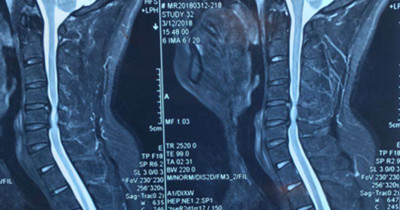

患者王先生,34歲,兩個月來自覺行走時雙下肢無力,伴踩棉花感,休息后癥狀無明顯緩解,雙手指麻木,呈加重趨勢。一月前就診于骨一科。確診為頸椎?。顾栊停?。病變部位位于頸5-6平面。

圖片一: